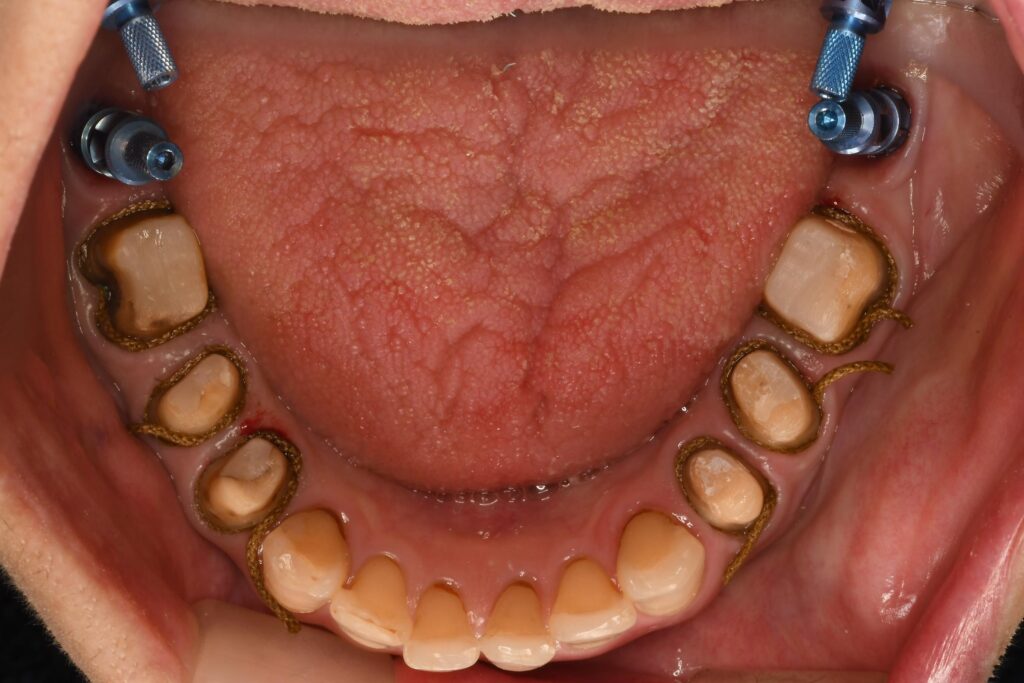

② 実際の表面麻酔の様子

実際に当院で行っている表面麻酔の様子をご紹介します。

▼ 写真挿入:表面麻酔を置いている様子

▼ 写真挿入:表面麻酔の上から、針を刺入している瞬間の写真